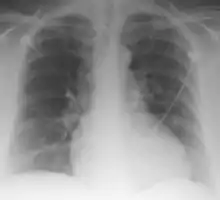

Palla's sign is a clinical sign in which an enlarged right descending pulmonary artery is seen on the chest x-ray in patients with pulmonary embolism. It is of low sensitivity, and its specificity is not known. It exhibits as a "sausage" appearance on X-ray. [1] It is named after italian radiologist Antonio Palla. In 1983, he published his observations that close to 25% of patients with pulmonary embolism had a chest x-ray sign of enlarged right descending pulmonary artery.[2][3]